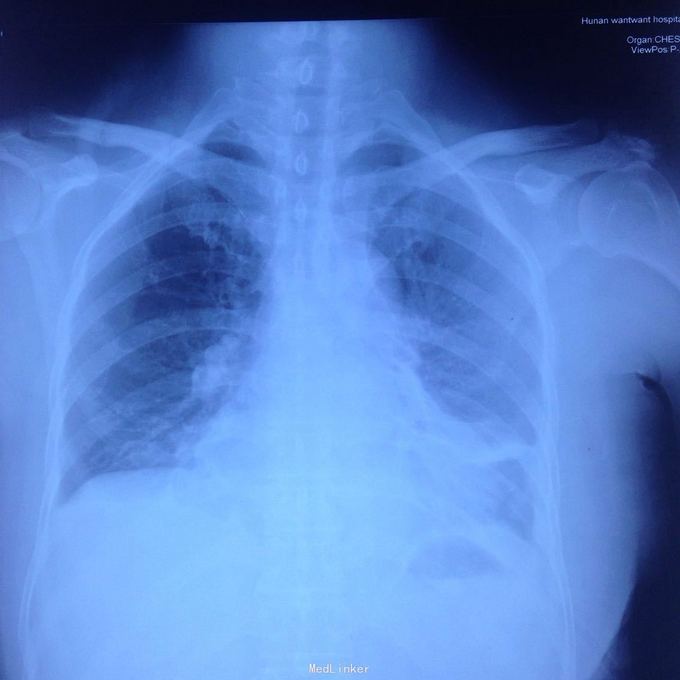

主诉:发现胸腔积液4月余。 现病史:患者4个月前因腰椎间盘突出在当地医院就诊,检查发现双侧少量胸腔积液,量不多,2个月后胸闷气短再次在当地医院复查胸部ct,提示双侧胸腔积液较前增多,左侧明显。

左侧胸腔包裹性积液? 完善胸腔b超提示左侧胸腔包裹性积液,最深处约59mm,内透声较差。予以定位后诊断性穿刺未抽出明显液体,当时考虑液体可能较粘稠或包裹分隔,遂决定予以小切口开胸探查。开胸后见胸腔积液,量约300ml,颜色较清亮,予以抽吸后在探查,见脏层及壁层胸膜无增厚及明显粘连,遂考虑不排除囊肿可能性,继续探查见胸膜顶靠近左纵隔处一囊壁,已破裂,囊壁挛缩成团,予以切除,术后病检为胸腺囊肿。

术后病检为胸腺囊肿。术后讨论:患者多次胸部ct均提示为包裹性积液,因囊肿较大,囊壁较薄,且靠近胸壁,易误诊为包裹性积液,但患者一直无发热病史,且复查ct积液位置靠胸前壁,术前应该考虑到囊肿可能,因患者经济较困难,至本院后未行增强ct,穿刺后考虑穿刺针将囊壁穿破,故开胸后未见完整囊肿,此类看似简单的病例容易由其他医院诊断误导,并且容易误诊。